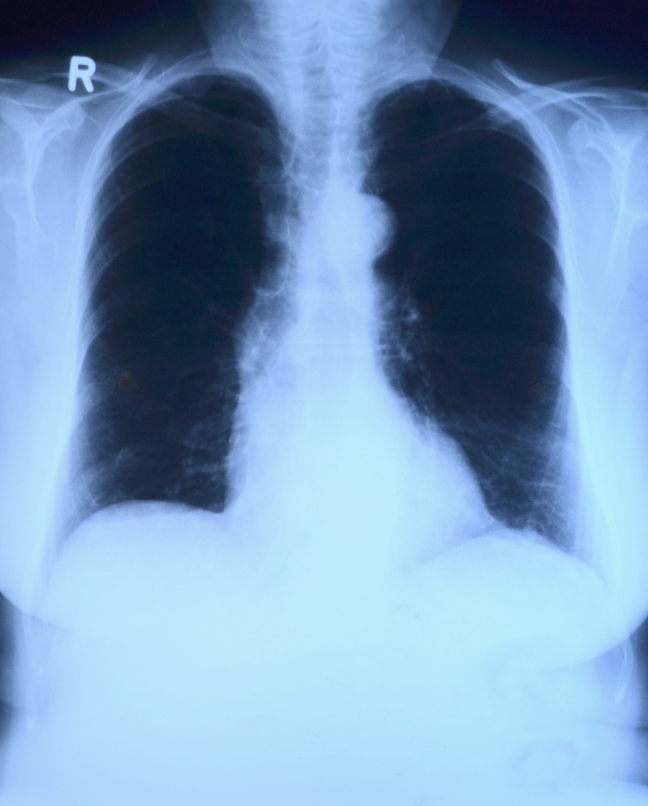

圖片來源:pixabay